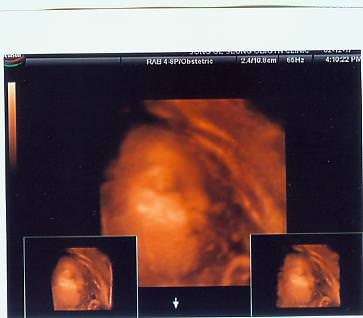

하니가 좋아하는 시저곰돌이랑..

달려라하니